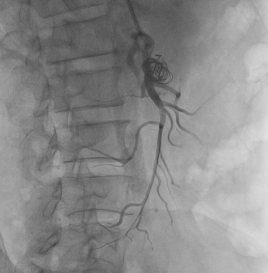

肠系膜上动脉夹层的手术风险高,可能出现术中血管破裂、术后肠道缺血等并发症,在与患者家属充分沟通后,首选腔内介入治疗。经过积极准备,在叶志东主任、樊雪强主任、郑夏医生、贺斌医生的共同努力下,对患者进行了肠系膜上动脉支架联合夹层动脉瘤栓塞治疗。支架释放成功,假腔显影明显减少,肠系膜动脉真腔供血改善,动脉瘤被“封堵”!

术中DSA造影